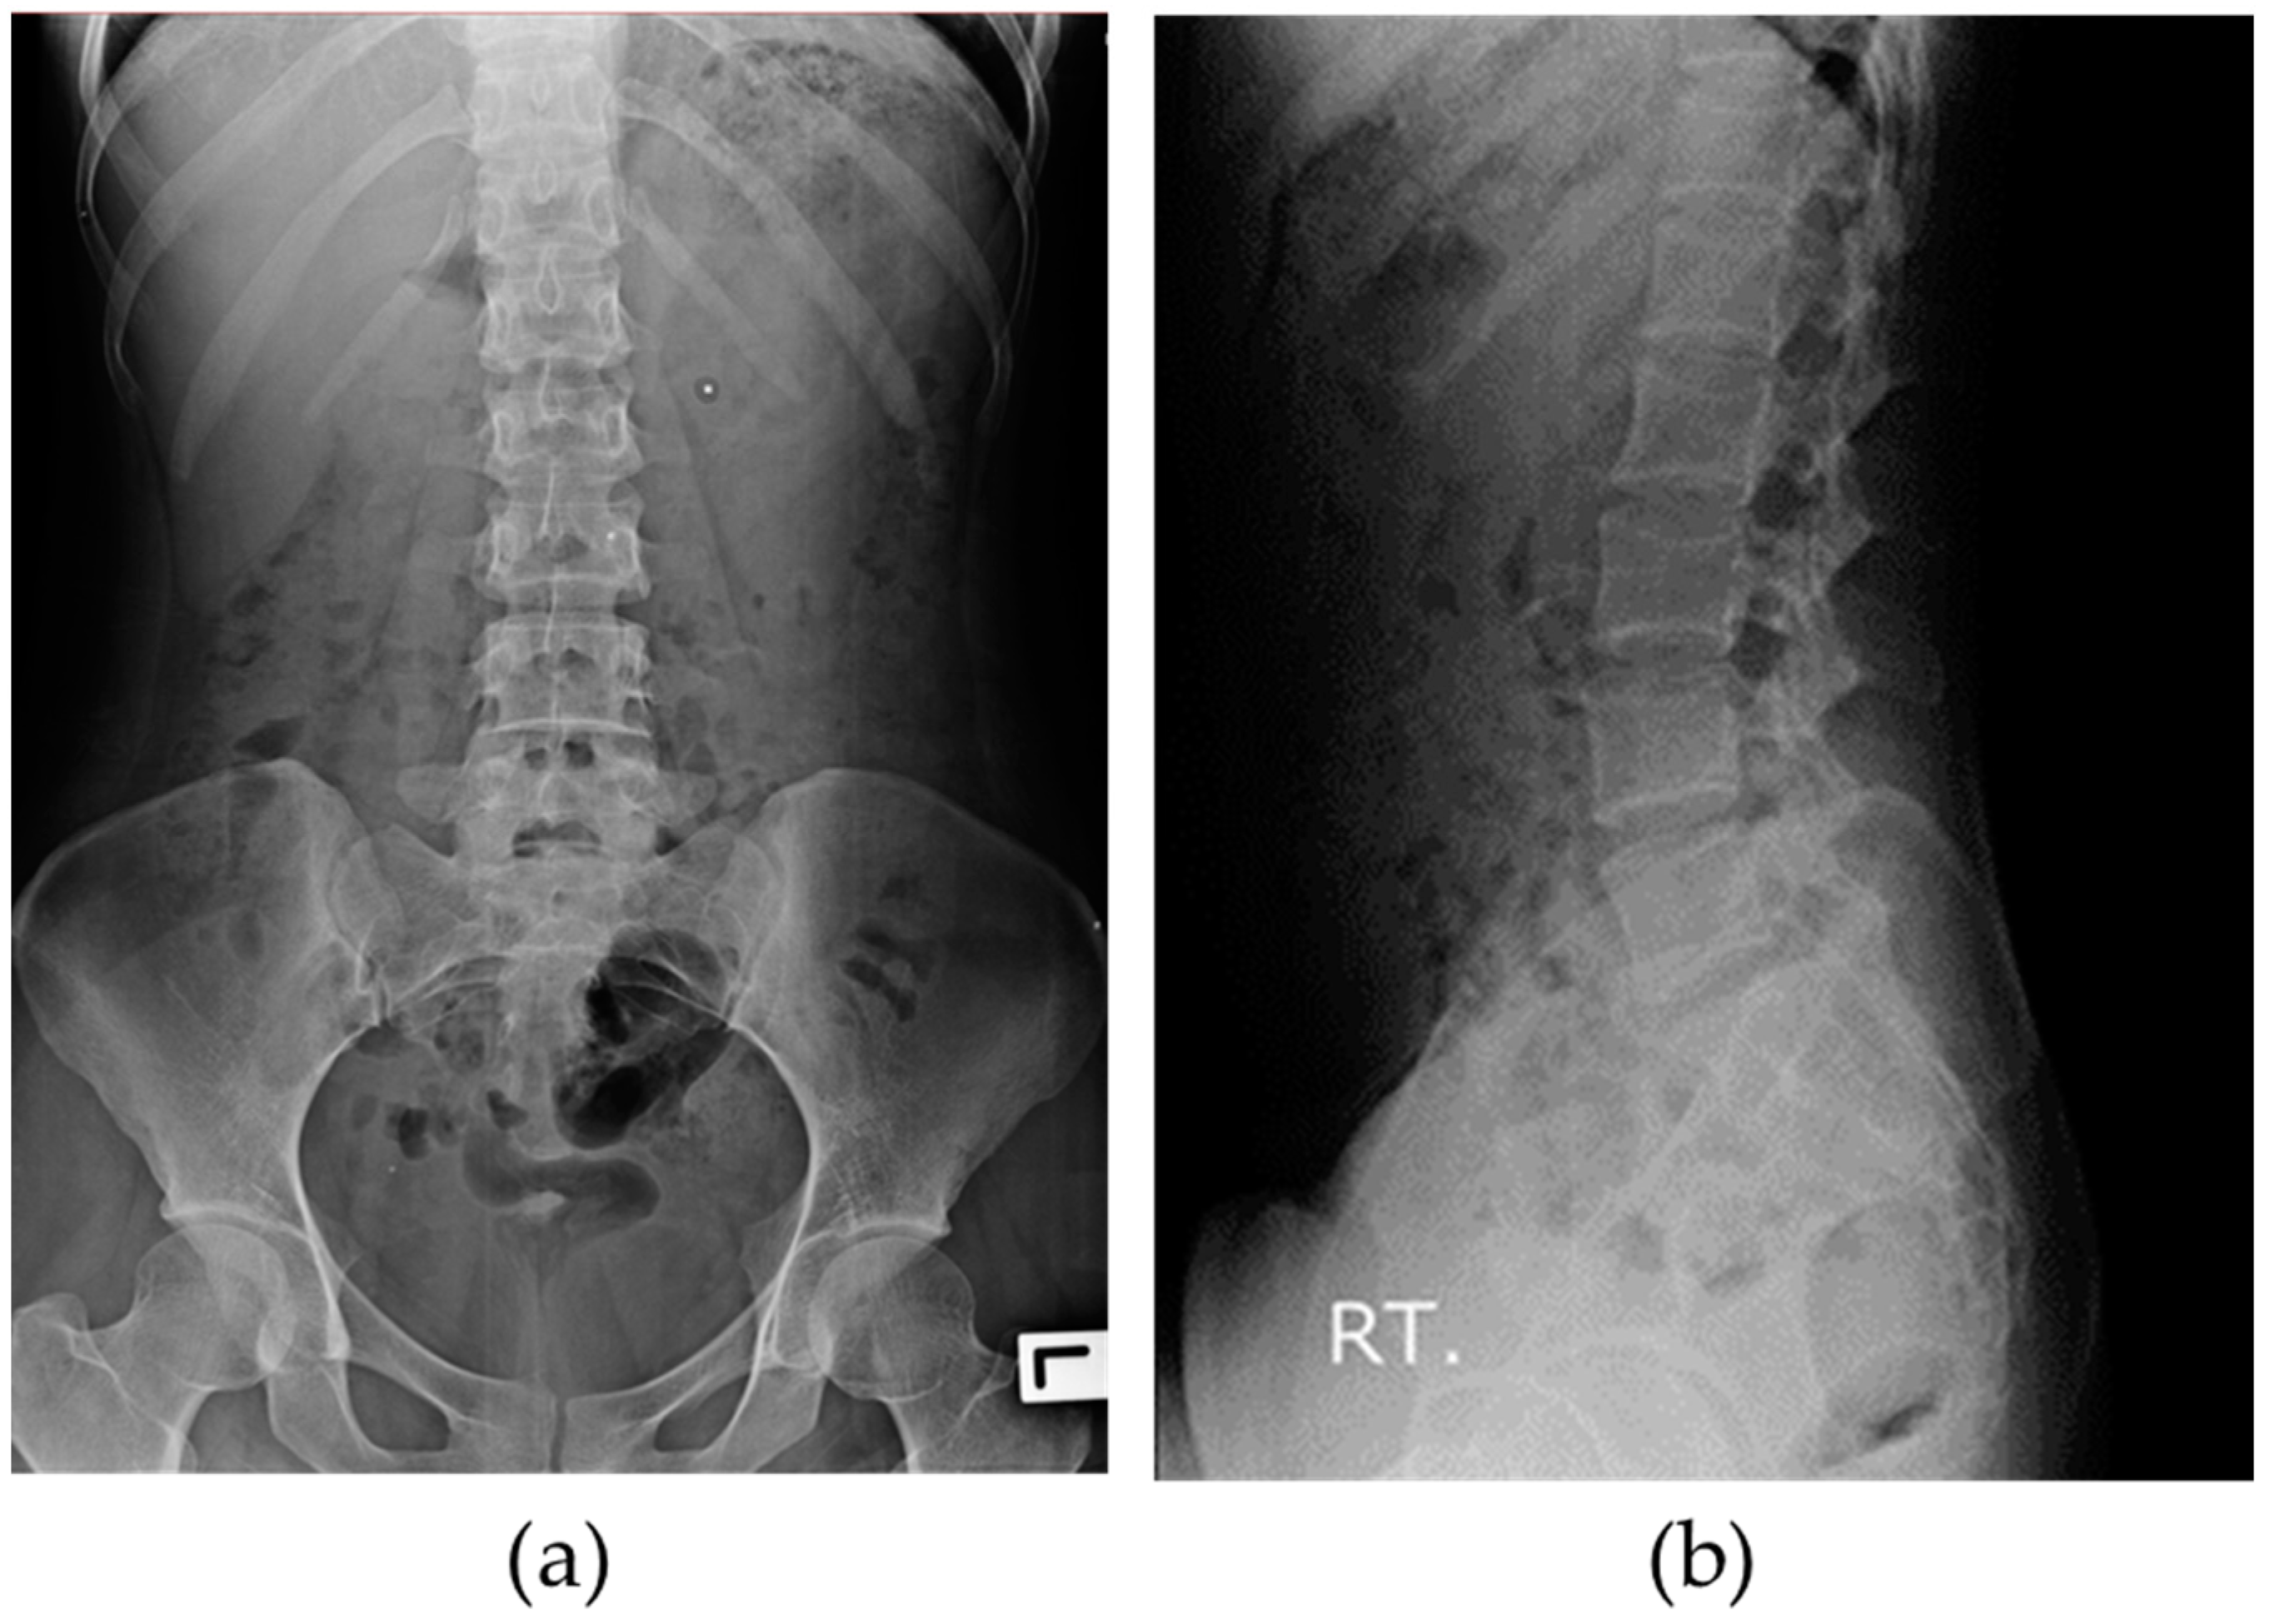

BUU-LSPINE is a collection of PF X-ray images of 3600 patients, as shown in Table 2. Each patient’s record has two views: an anteroposterior (AP) and a lateral (LA), as shown in Figure 1. Our dataset of 3600 patients comprises 7200 images because each has two views. All lateral images were flipped to face the left side. A record of our dataset includes two JPG X-ray images and two CSV ground truth files. Our dataset consists of three ground truths: vertebral position, spondylolisthesis, and LSTV. Further elaboration on the ground truths is provided in the following section.

Figure 1.

X-ray images in BUU-LSPINE: (a) anteroposterior (AP) view; (b) lateral (LA) view.